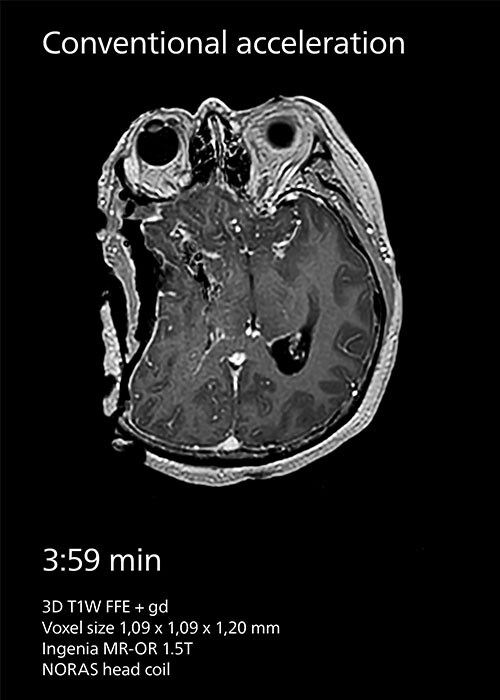

Compressed SENSE reduces scan time from 3:59 min to 2:55 min with the same spatial resolution.